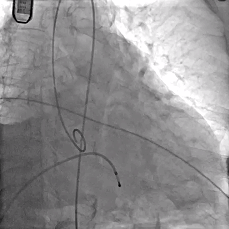

手术过程

主动脉根部造影

TF29瓣膜,0位定位释放

瓣膜稳定释放至全展开

造影观察

瓣膜位置可,形态佳

左冠切线观察,瓣膜位置可,冠脉灌注良好